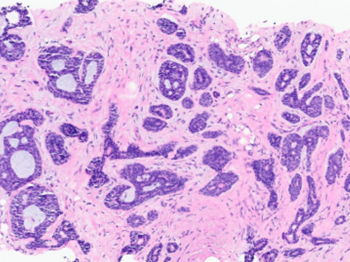

A 40 y/o euthyroid female and a 3 cm left-sided thyroid nodule incidentally found.